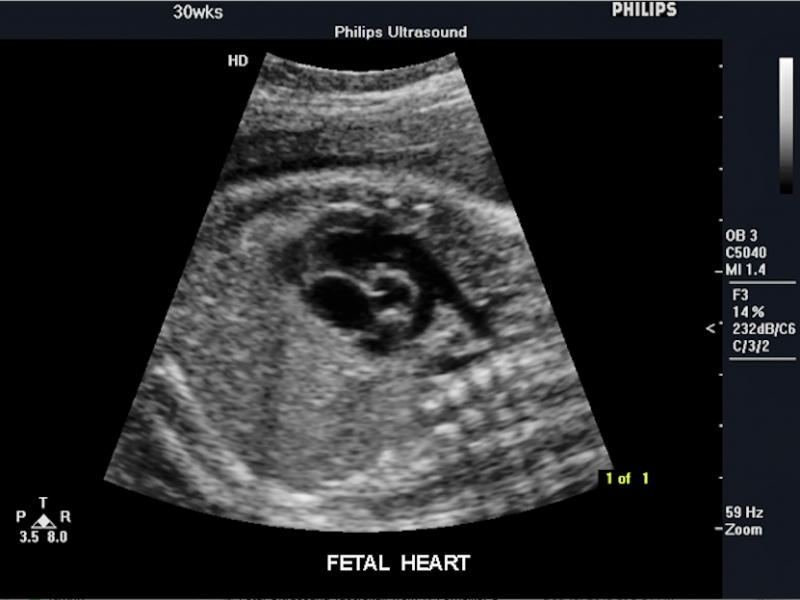

Below is a collection of prenatal ultrasound pictures from the Imaging Technology News (ITN) archive. Use the arrows to click through the image gallery. It includes transvaginal ultrasound images and fetal echocardiogram images. Fetal imaging is referred to by many names, including pregnancy sonograms, pregnancy ultrasound, endovaginal ultrasound, obstetric ultrasound, OB ultrasound, baby ultrasound, prenatal ultrasound. Fetal heart ultrasound is also called baby echo or prenatal echo.